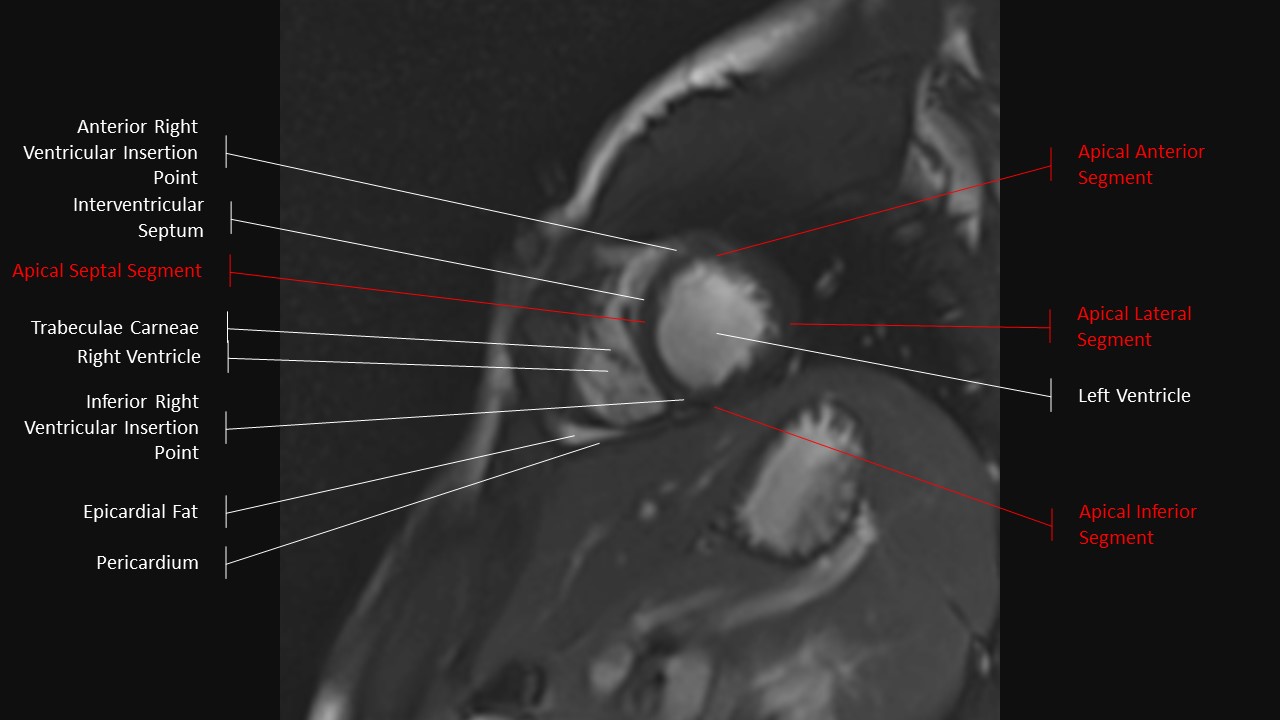

Short Axis Series